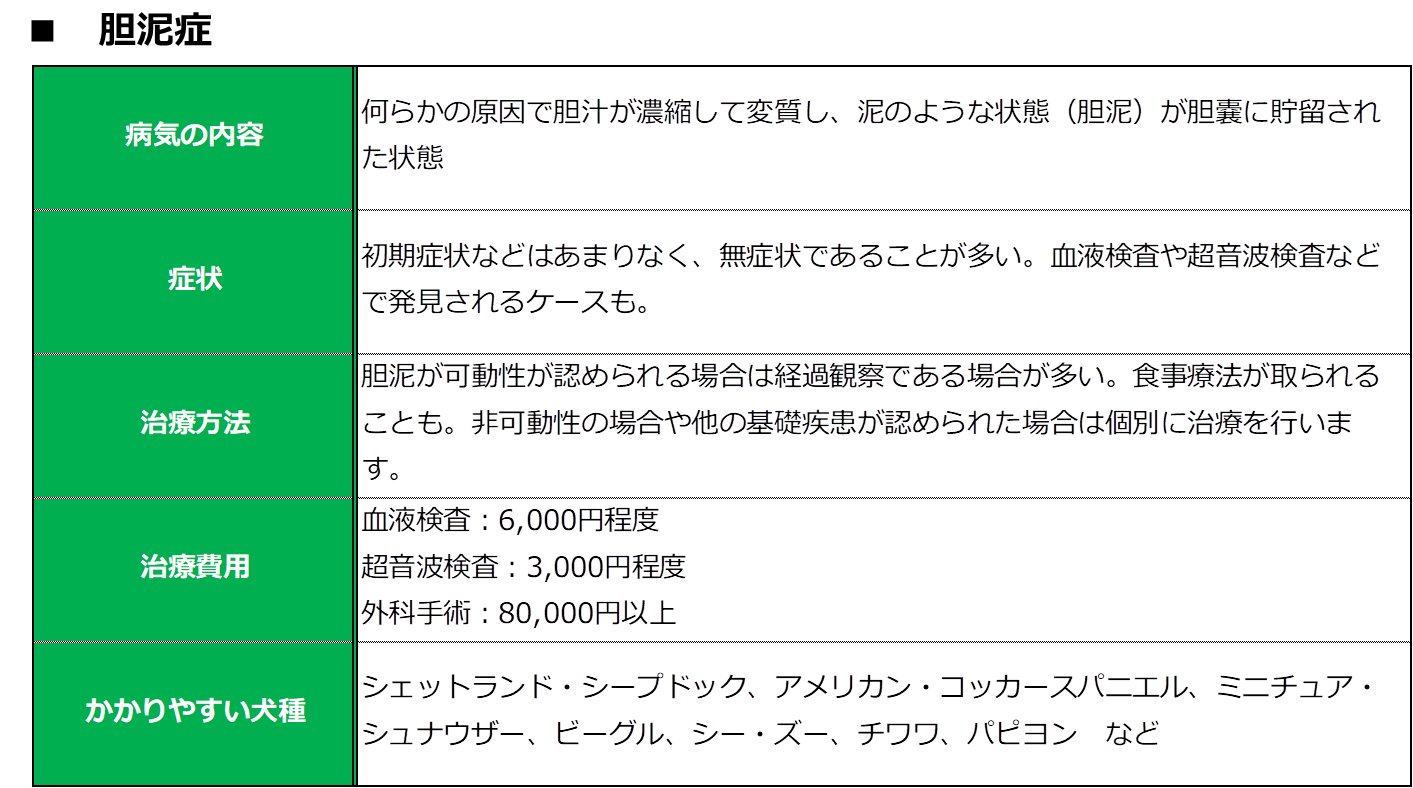

胆泥症は無症状で経過することが多いため、定期的な健康診断で早期発見を心がけましょう。 また、胆嚢炎や内分泌疾患( 甲状腺機能低下症 や 副腎皮質機能亢進症 )などのような、

犬 胆泥症 原因-胆泥 をかたちづくっているのは コレステロール や 黄疸色素 ( ビリルビン )、 カルシウム などの微細な 結晶 が 胆嚢壁 から分泌される 粘液 に包まれたものと考えられますが、他にも 炎症 によっこんにちは。獣医師の清水いと世です。 今回は、わんちゃんの胆泥症について説明します。 前編は、胆泥症の原因や検査方法や症状について、後編は治療や予防方法について説明します。 犬の胆泥

胆泥症・胆石症について 胆嚢は、胆汁を産生し貯留する器官です。 胆汁には、脂肪を分解し水に溶けやすい状態に(乳化)する役割を持っています。 胆嚢に貯えられた胆汁は、元々サラサラの水胆泥を生じさせた原因や疑われる原因があれば、それを取り除きます。 そのために、 犬の胆泥症 <前編> で説明した原因追及のための検査結果が重要になります。 肝臓の異常が認められるので